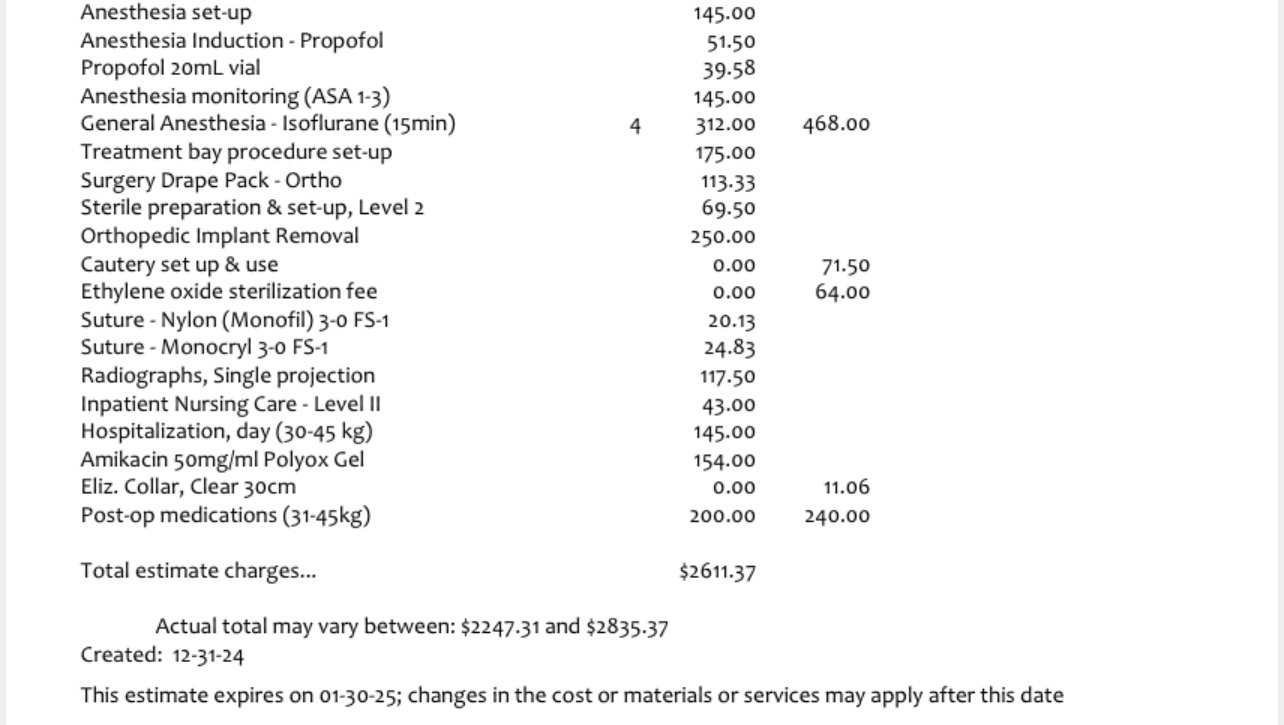

He began to be non-weight bearing on his leg. After several veterinary opinions, imaging, and medication trials, it was determined that the hardware that was placed in Titus leg, was now causing him an infection. So the orthopedic surgeon has said we need to remove the hardware.

Since long term antibiotic use isn’t something that is recommended, surgery is something that is needed, soon.